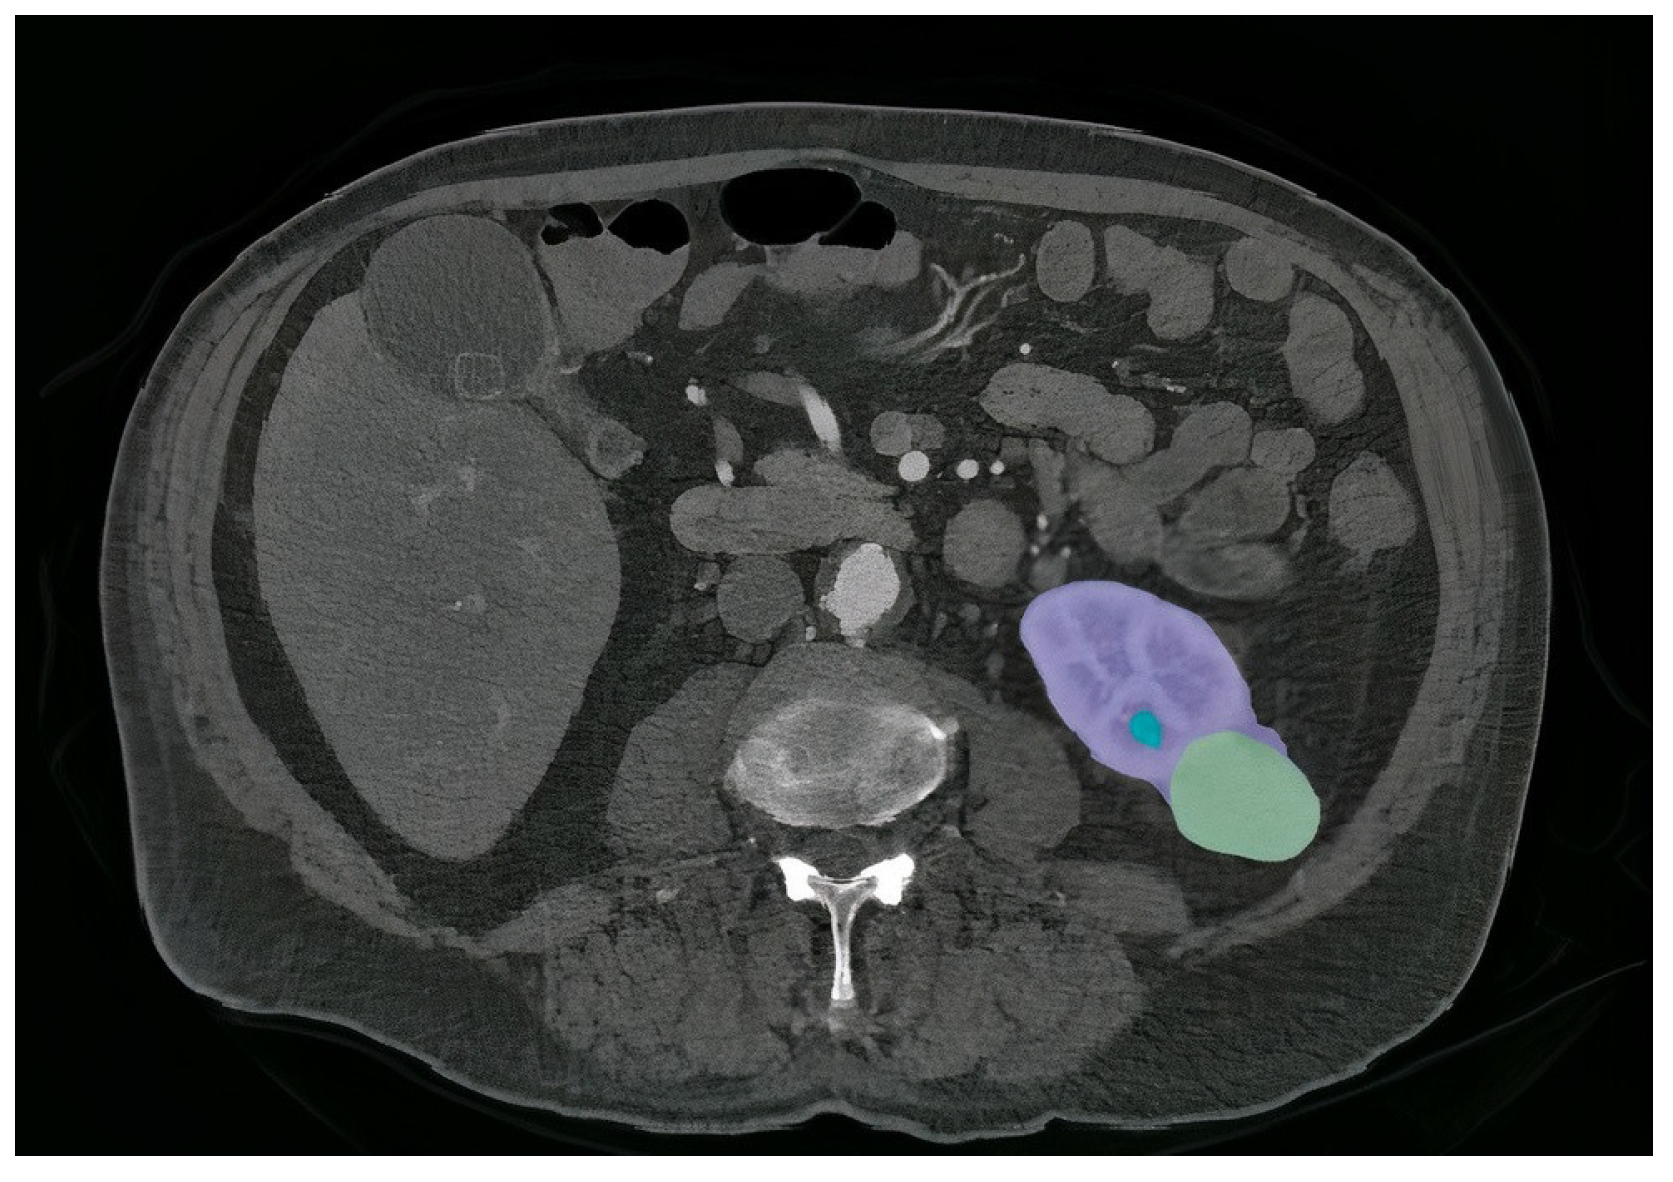

4.4. Incorporating GCAM-Attention Fusion to UNet-PWP on CT Scan